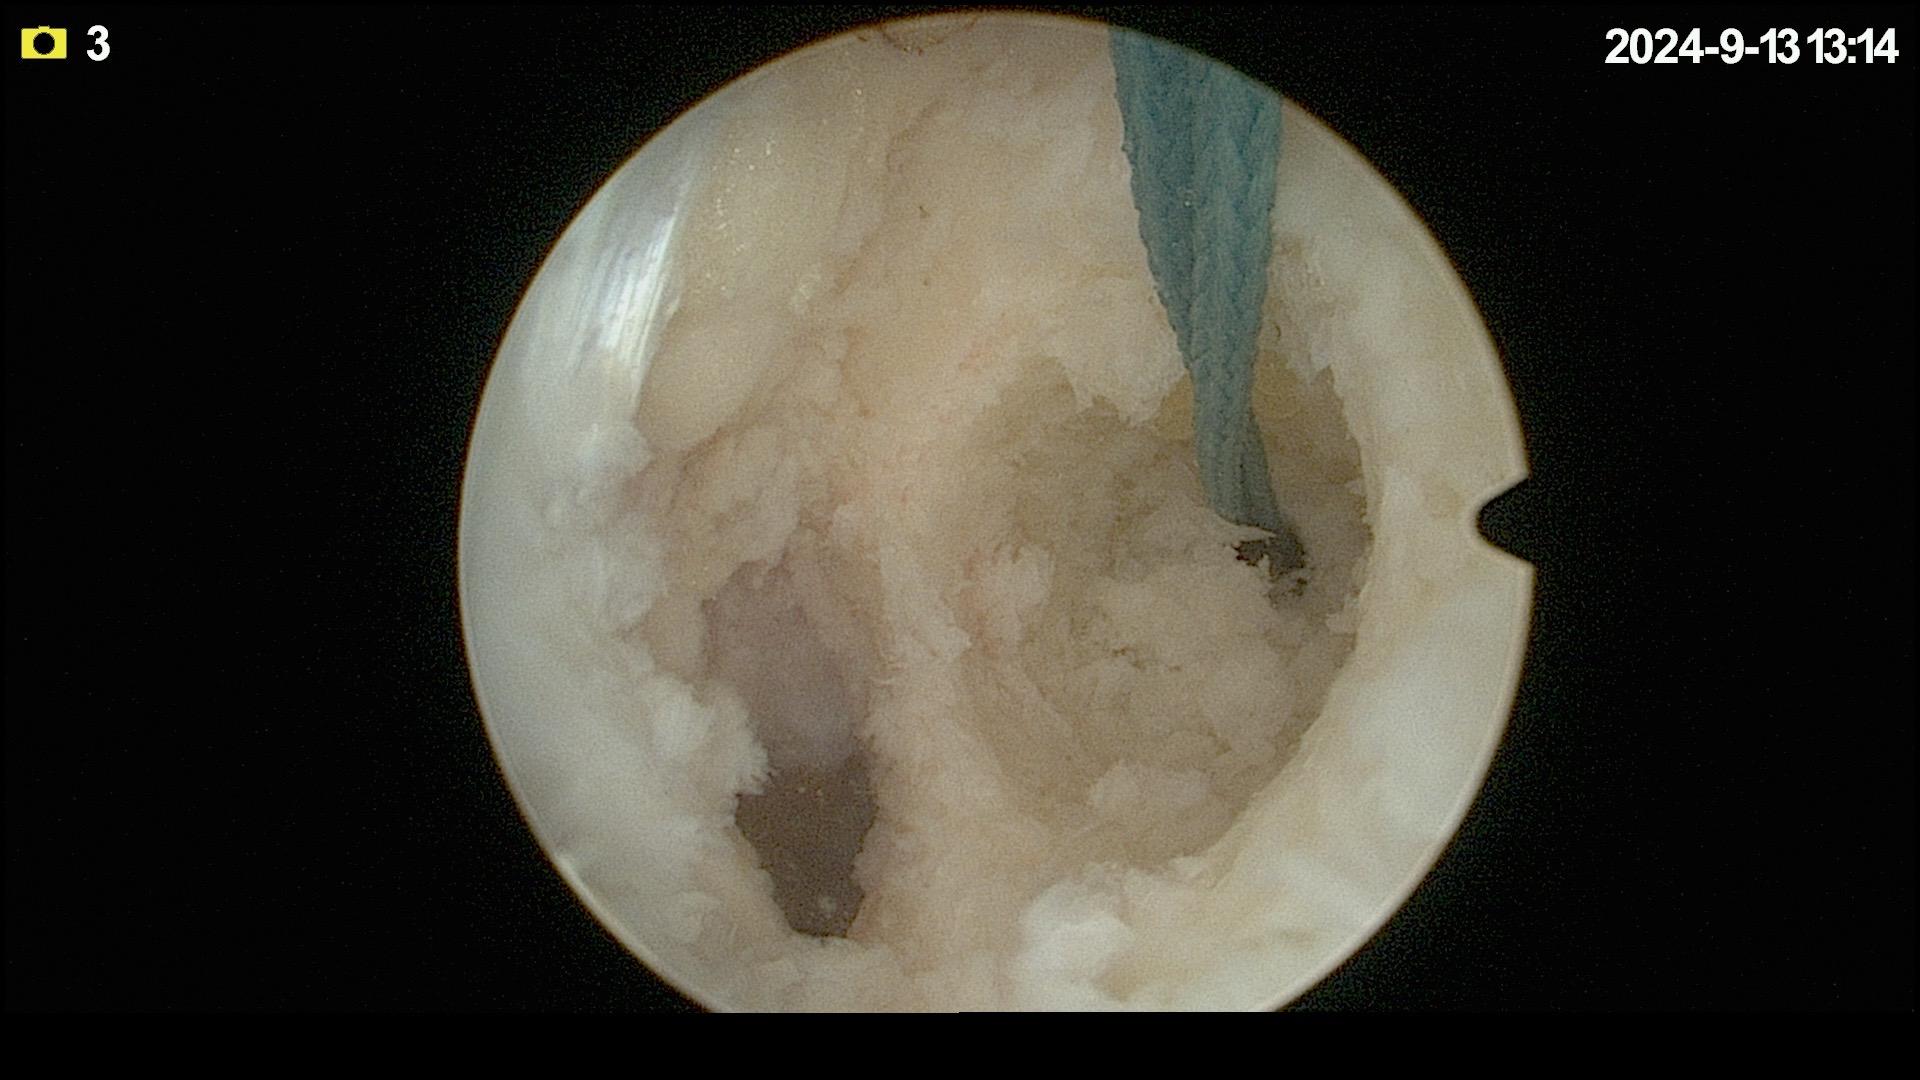

前交叉韧带重建。面对前交叉韧带的断裂,我们选择重建。希望这根强大的移植体,能为他撑起一片天,让他再次在运动场上放飞自我。前交叉韧带重建 前交叉